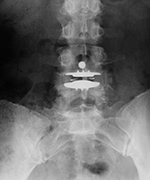

| Metal-on-polyethylene total disk replacement at L4-5 |

| 46 year-old woman with degenerative disk disease. There is also a ligamentous fixation screw at L4. |